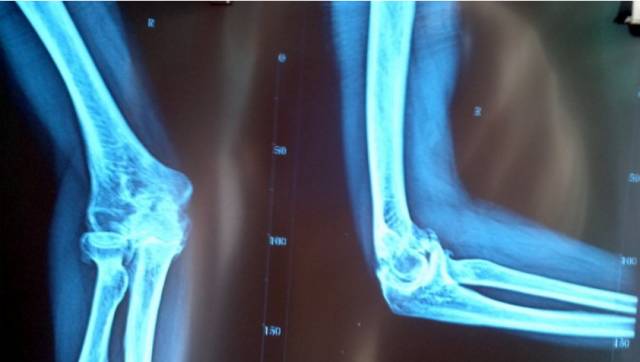

由肱骨下端与尺、桡骨上端构成的复合关节, 包括3个关节。

(1)肱尺关节 由肱骨滑车和尺骨滑车切迹构成,属于滑车关节。

(2)肱桡关节 由肱骨小头和桡骨关节凹构成,属球窝关节。

(3)尺桡近端关节 由桡骨环状关节面和尺骨桡切迹构成,属于车轴关节。

3个关节共同包绕在一个关节囊内, 关节囊的前后壁相对松弛. 以关节囊的后壁最为薄弱,两侧壁增厚而且紧张,并有韧带加强。

肘关节的运动功能以成肱尺关节为主,主要在冠状轴上做屈、伸运动,伸前臂时,前臂偏向外侧,构成约为10°的外偏角,称为肘关节提携角。

当肘关节伸直时,肱骨内、外上髁和尺骨鹰嘴三点在一条直线上, 当关节屈曲至90度时, 此三点的连线构成一个尖向下的等腰三角形 。